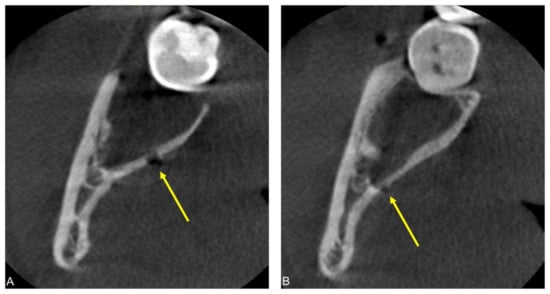

2.1. Case 1